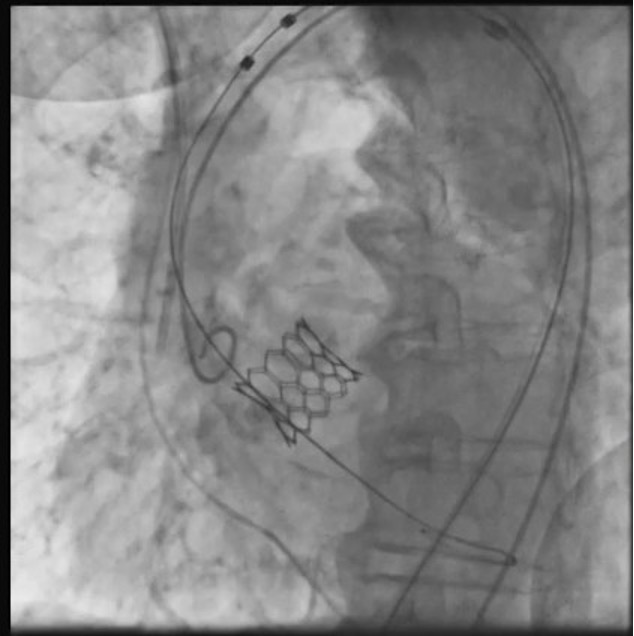

The patient was taken up for TAVR via a left common femoral artery (CFA) approach. The aortic valve was crossed (Figure 1A), and pre-dilatation was done using an 18-mm x 40-mm Mammoth balloon catheter (Meril Life Sciences) (Figure 1B). A 24.5-mm Myval transaortic valve (Meril Life Sciences) was introduced inside a Python expandable introducer sheath (Meril Life Sciences). However, the device could not be negotiated in the distal external iliac artery (EIA) due to calcium. The arrow in Figure 2A shows calcium in the distal EIA. The artery forceps depicts a marker for the distal end of the Python sheath. The sheath was withdrawn in the distal EIA; right CFA puncture was done and a 7F crossover sheath was placed. Intravascular lithotripsy (IVL) was done using a 7-mm x 60-mm IVL balloon; 30 pulses at 4 atm followed by 30 pulses at 6 atm were given (Figure 2B).

Following this, the sheath could be advanced proximally and the 24.5-mm Myval transaortic valve was negotiated and deployed (Figure 2C). A check angiogram showed good flow across the common iliac artery and EIA with no dissection (Figure 3). The puncture site was closed using a Perclose ProGlide Suture-Mediated Closure System (Abbott Cardiovascular). n